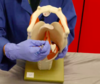

What is this bone?

Mandible

What is this bone?

Hyoid

What is this?

Thyroid cartilage (esp. laryngeal prominence/Adam’s apple)